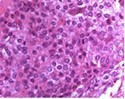

Upon microscopy, tumefaction is significantly cellular and composed of sheets of spherical to polyhedral chondroblastic cells imbued with abundant, eosinophilic cytoplasm and well demarcated cellular perimeter. Intracytoplasmic glycogen granules are evident. Nuclei appear elliptical, hyper-lobulated and demonstrate nuclear grooves. Nuclear atypia appears insignificant 1, 2.

Focal aggregates of spindle-shaped cells may be enunciated. Peri-cellular zones of ‘lace-like’ or ‘chicken wire’ calcification appear intermingled with degenerative chondroblasts. Eosinophilic foci of chondroid matrix are invariably discerned 1, 2.

Focal mitotic activity, necrosis and osteoclast-like giant cells may be commingled with cellular zones. Besides, aneurysmal bone cyst-like modifications are commonly observed 1, 2.

Figure 1.Chondroblastoma demonstrating round to oval chondroblastic cells with abundant, eosinophilic cytoplasm and vesicular grooved nuclei encompassed within a myxochondroid matrix5.